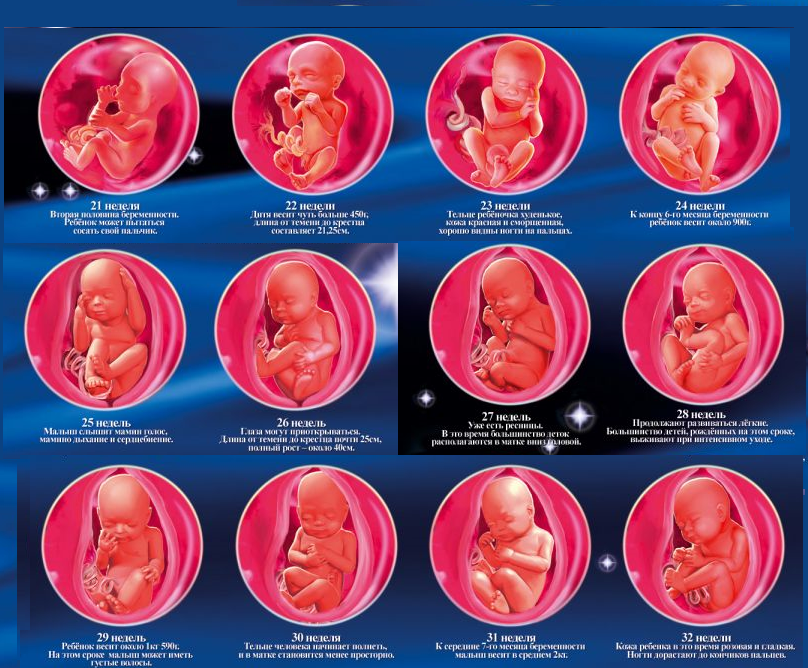

Фотография Плода В Животе

Фотография Плода В Животе 113 фотографий